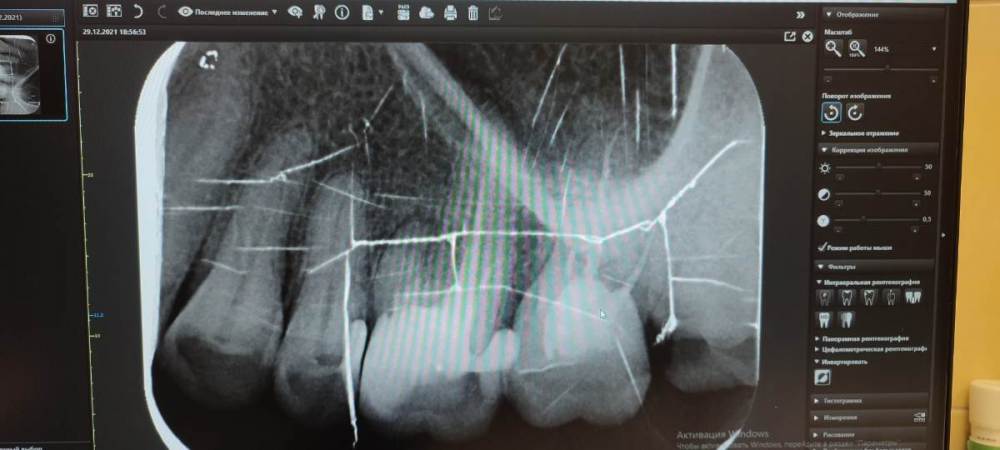

Люлякебаб Опубликовано 30 декабря, 2021 Поделиться Опубликовано 30 декабря, 2021 Здравствуйте, уважаемые специалисты! Зуб шестёрка верхняя. Были прочищены каналы. Поставлена пломба. Лет 10 назад. Сколько-то лет назад на десне в районе зуба появился бугорок в диаметре около 5 мм. В последнее время зуб реагирует на горячее и холодное. Иногда болит, но проходит. По снимку врач увидела, что не всё каналы прочищались. Советует найти специалиста по прочистке каналов под микроскопом. Другая врач общей практики считает разумным только удаление и последующую имплантацию. Я в замешательстве. Первый вариант невероятно дорог. Второй рискован, впрочем, как и первый. Что делать? Ещё между пятёркой и шестёркой этой я зубочисткой нащупываю неровности с резкой болью и запах (извините за подробности). Ссылка на комментарий

It'sGeorgy Опубликовано 18 января, 2022 Поделиться Опубликовано 18 января, 2022 (изменено) Добрый день. 30.12.2021 в 20:32, Люлякебаб сказал: Что делать? Начните с КТ. И для диагностики, и для возможного перелечивания, и для возможной имплантации вам она все равно потребуется. 30.12.2021 в 20:32, Люлякебаб сказал: Ещё между пятёркой и шестёркой этой я зубочисткой нащупываю неровности с резкой болью и запах (извините за подробности). Судя по предоставленному снимку с пятеркой тоже могут быть проблемы. Не исключено, что беспокоит вас именно она. Изменено 18 января, 2022 пользователем It'sGeorgy 1 Ссылка на комментарий

dentikl Опубликовано 18 января, 2022 Поделиться Опубликовано 18 января, 2022 снимок тертый,но мне видится выпавшая пломба в 8 1 Ссылка на комментарий

Irouil Опубликовано 19 января, 2022 Поделиться Опубликовано 19 января, 2022 Сделайте КТ, будет больше пищи для обсуждения пока что те жалобы, что Вы предъявляете, более характерны для живых зубов, а таких подозреваемых 2 - соседняя 5-ка и 8-ка 1 Ссылка на комментарий